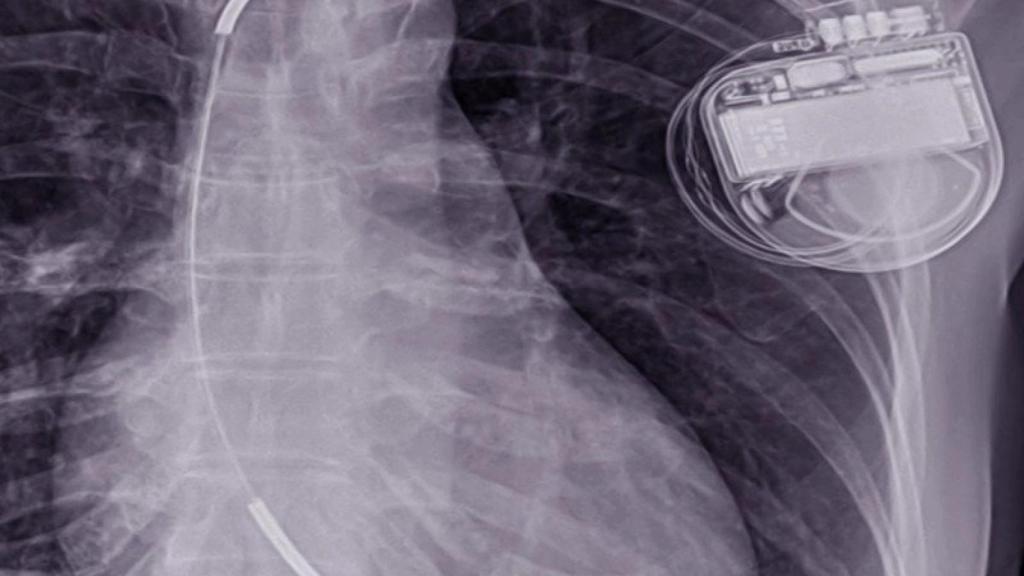

Un DAI (desfibrilador automático implantable) en una radiografía

Un DAI (desfibrilador automático implantable) en una radiografía Cirugía Cardiovascular Sevilla

No hay que confundir este dispositivo con un marcapasos. El doctor Juan Carlos González explicó a EL ESPAÑOL tras lo sucedido con Eriksen que el DAI tiene función de marcapasos (suple nuestro propio sistema eléctrico si no funciona) pero además, detecta si el corazón va más rápido (sufre taquicardia o arritmia rápida) y pueden llegar a producir muerte súbita. En ese momento puede detectarla y enviar estímulo para que acabe.

El desfibrilador se encarga de controlar el ritmo cardiaco y detectar una arritmia maligna. Cuando la percibe actúa automáticamente. Lo puede hacer de dos maneras: con una estimulación que aumente el ritmo con el que se ataje la arritmia, o en un caso más grave y extremo con una descarga eléctrica. Esta variante necesita de una visita posterior al médico, como le sucedió a Dwamena durante el partido en Austria. Eriksen vuelve al fútbol, pero no lo hace solo ya que este será su gran aliado.